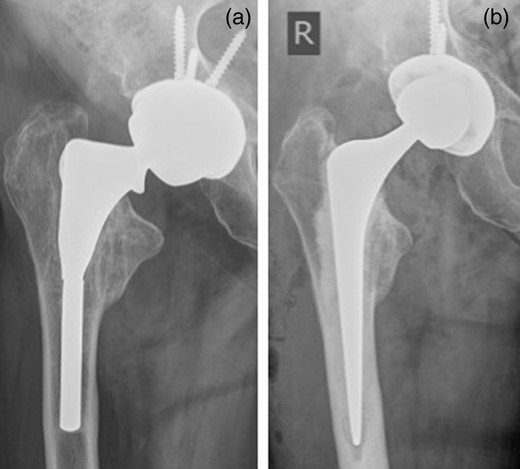

In both cases, there was evidence of significant osteolysis in the proximal femur (Fig. 3); microbiological testing of intraoperative specimens was sterile. The proximal part of each stem was loose and easily removed (Fig. 4). The distal stems were well fixed and were extracted antegrade using trephine (DePuy Moreland Cementless Extraction System, Leeds, UK) without osteotomy. In this technique, the trephine is used to ream the cement mantle around the distal portion of the stem till either the stem is trapped within the trephine, and can then be removed with it, or an appropriate space is made for a grasper to be introduced to remove the stem. The outcome was excellent for both cases with immediate pain relieve and no early complications. The oxford hip scores were 43/48 for Case 1 at 5 months and 36/48 for Case 2 at 4 months.